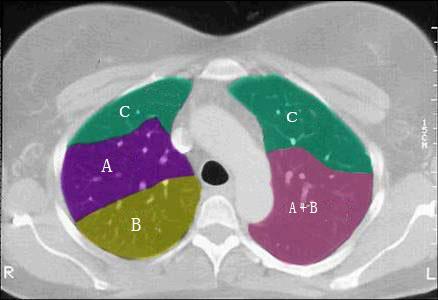

结合肺段模式肺动脉干与右肺动脉层面(如图),选出右肺中叶的组成 ( )A.BB.B+CC.B+C+DD.D+EE.D+E+F

问题 结合肺段模式肺动脉干与右肺动脉层面(如图),选出右肺中叶的组成 ( )

选项 A.B B.B+C C.B+C+D D.D+E E.D+E+F

答案 D